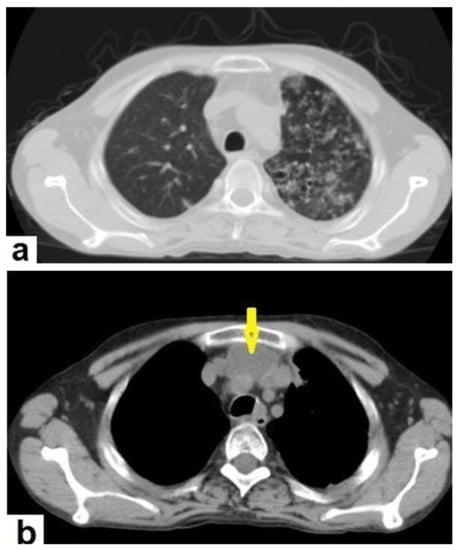

• Miliary TB (Figure 6 and Figure 7) appears as innumerable small (1–3 mm) granulomas with random distribution in the lungs and other organs with a predominance to the lung bases due to the gravity-dependent high blood flow. It occurs due to the hematogenous dissemination of mycobacterium tuberculosis bacilli, especially in immunocompromised patients and children [1,13]. Miliary TB is a significant differential diagnosis of pulmonary metastasis from thyroid cancer or others, even in children [19].

Figure 6. Miliary TB in an 18-year-old man (same patient of Figure 1). (a) Chest radiograph shows superimposed innumerable small nodules in lungs right greater than the left predominantly affecting lung bases due to gravity-dependent high blood flow. (b) Axial chest CT shows innumerable small (1–3 mm) nodules with random distribution in both lung fields.